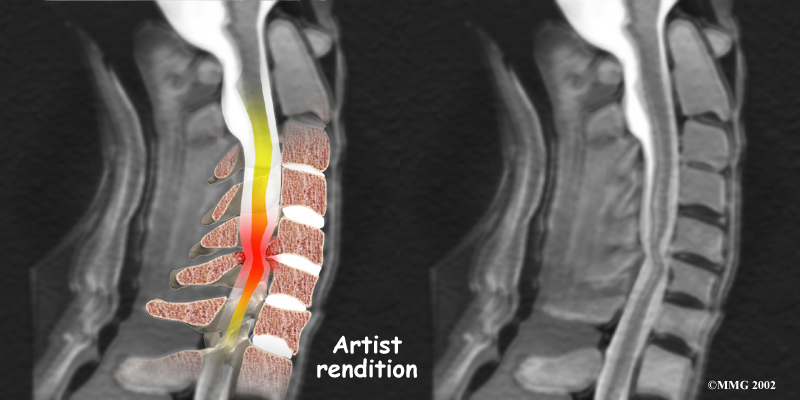

MRI

The magnetic resonance imaging (MRI) scan uses magnetic waves to create pictures of the cervical spine in slices. The MRI scan shows the cervical spine bones, as well as the soft tissue structures such as the discs, joints, and nerves.

MRI scans are painless and don't require needles or dye. The MRI scan has become the most common test to look at the cervical spine after X-rays have been taken.